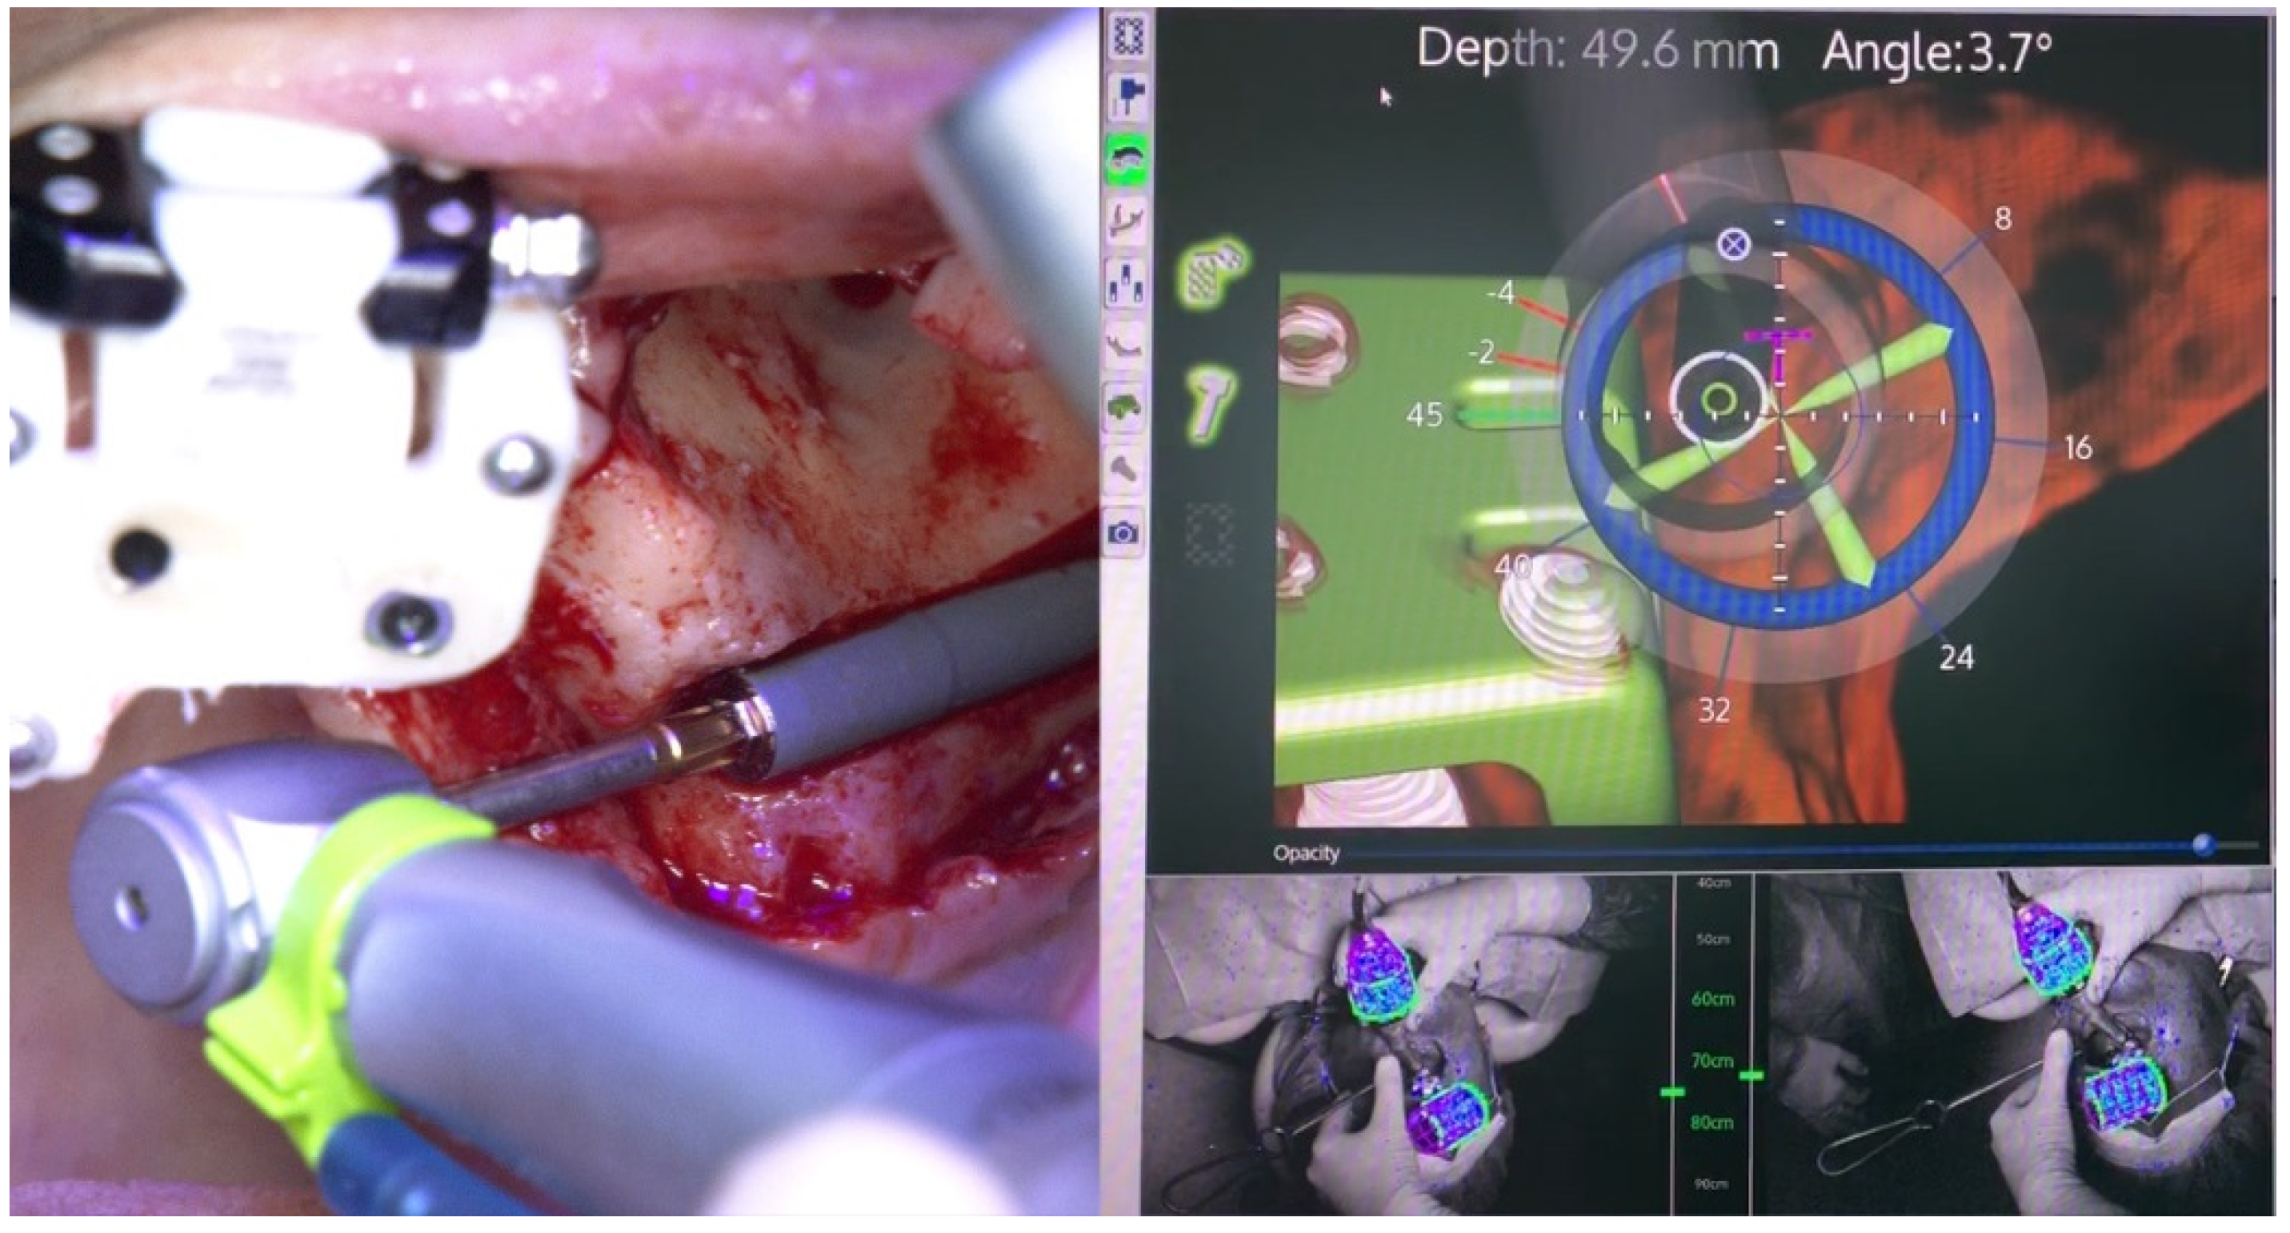

2.1. Patient 1

2.2. Patient 2